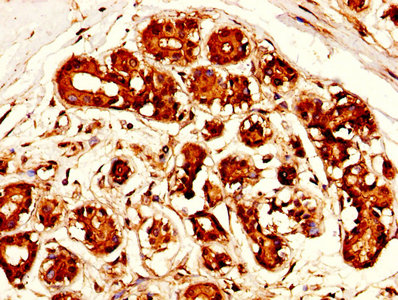

• IHC image of CSB-PA10159A0Rb diluted at 1:300 and staining in paraffin-embedded human ovarian cancer performed on a Leica BondTM system. After dewaxing and hydration, antigen retrieval was mediated by high pressure in a citrate buffer (pH 6.0). Section was blocked with 10% normal goat serum 30min at RT. Then primary antibody (1% BSA) was incubated at 4°C overnight. The primary is detected by a biotinylated secondary antibody and visualized using an HRP conjugated SP system.